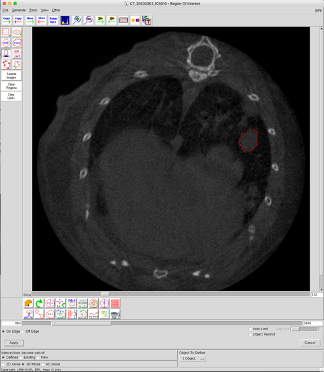

2. Select the file and click on Region Of Interest (ROI)… to open it

3. Select Auto Trace

4. Click in the middle of the tumor (ROI) to analyse

5. Adjust the threshold with the cursor that appears to encircle the entire ROI

6. Click on Apply

7. In the Object To Define section, select x.Object (x being a digit) to define the tumor (ROI)

8. Click on Copy Current Region Forward or on Copy Current Region Backward to encircle the entire tumor volume.

! On each slice, adjust the ROI using Add Trace Limit to encircle the entire tumor

! Repeat the step 8 on each slice on which you detect the tumor to follow

Figure A. Example of tumor volume analysis using Analyze 12.0.

A lung tumor-bearing slice with a Region of Interest (ROI) (=tumor) encircled in red.